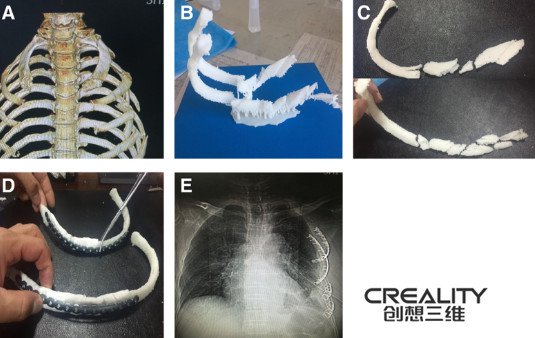

研究人员使用3d打印机改善肋骨骨折手术 创想三维 国内3d打印机生产厂家 工业3d打印机多少钱 3d打印机的价格 3d打印机diy 大型 创想三维

研究人员通过3d打印机改善肋骨骨折手术 中国3d打印机网

研究人员通过3d打印机改善肋骨骨折手术 中国3d打印机网